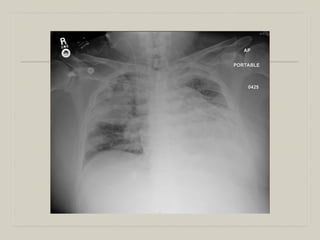

  84 BM (DM, AF, CAD ESRD on PD) in & out of hospitals

with peritonitis now admitted with peritonitis. He has an altered

MS, intubated for 4 days. Antibiotcs. He returns to the ICU

with fever 101F, altered MS, respiratory difficulty and is

intubated.

  Temp 101F, BP 80/-, HR 99.

  PaO2/FiO2 200

  WBC 3.2 Hgb 8 gm/dl, Plt 23K.

  Bronchosocpy with BAL: GNR 105 cfu.